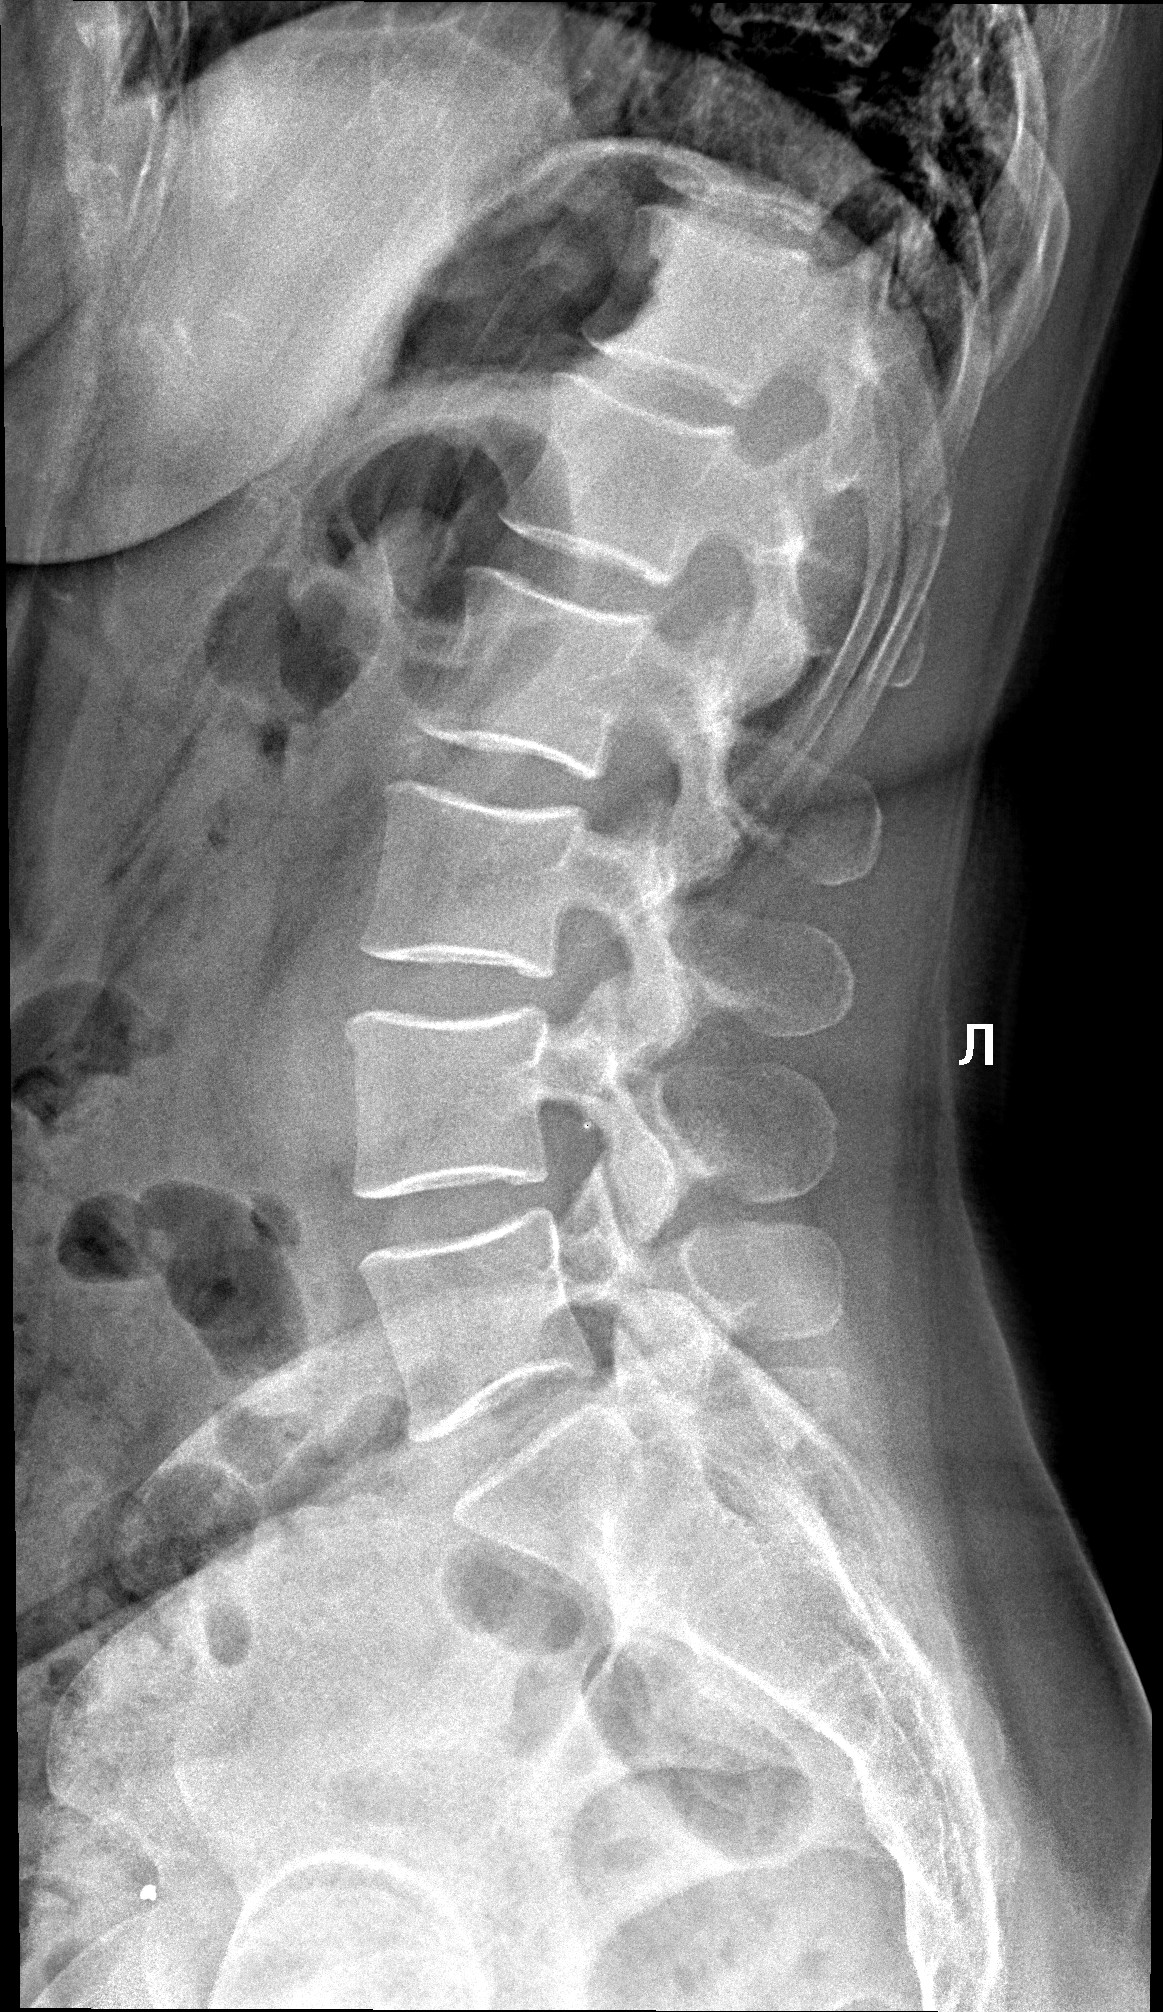

Рентген поясницы: анатомические особенности и медицинские исследования